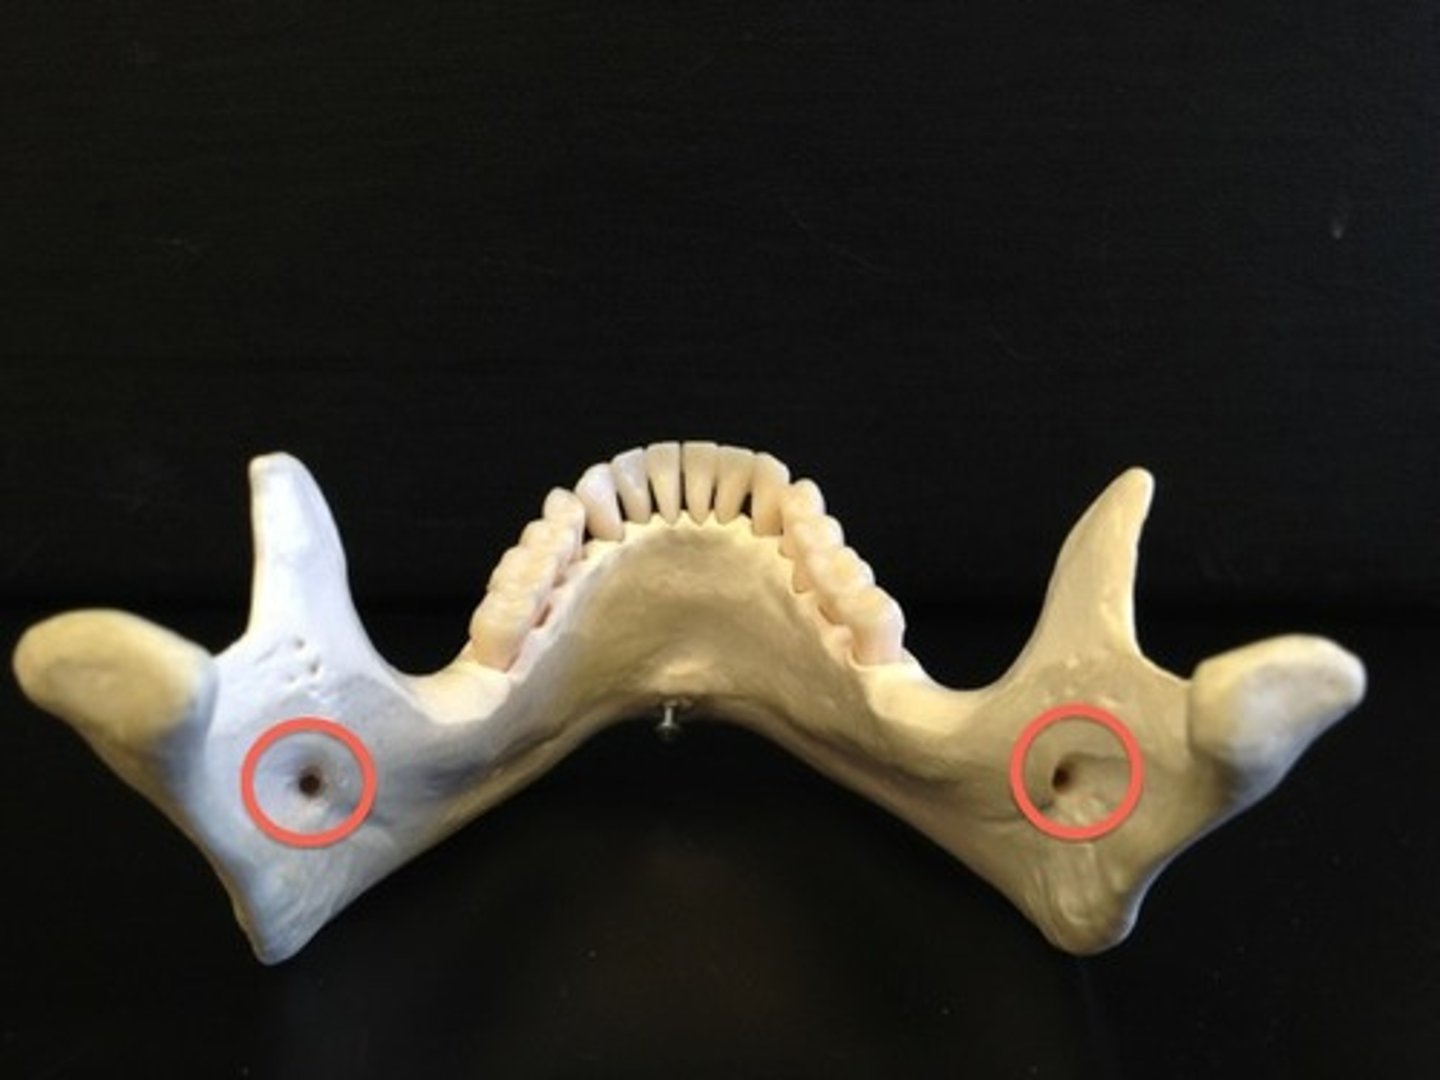

Mandibular foramen